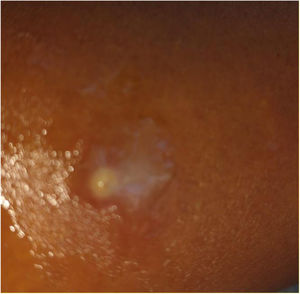

En la exploración física se observa edema difuso en el brazo izquierdo, especialmente en el tercio medio, asociado a rubor intenso, aumento de la temperatura local y dolor a la palpación, compatible con clínica de celulitis. La piel presenta induración y una zona central más dolorosa, donde se aprecia un punto erosionado. A pesar del dolor, no se observa fluctuación ni signos claros de colección purulenta. No se identifican lesiones cutáneas evidentes que actúen como puerta de entrada. La movilidad del brazo está conservada y no se detectan alteraciones neurovasculares distales. En la figura 2, se puede observar el punto central abierto con secreción amarillenta y eritema circundante, características del punto de inserción de la miasis cutánea.

Finalmente, el día 23 desde el inicio del tratamiento, desde la zona del punto erosionado se expulsó de forma espontánea una estructura móvil, que fue recuperada por el paciente y posteriormente analizada, identificándose como una larva del género Calliphora (Diptera: Calliphoridae). Posteriormente, la herida evolucionó hacia la resolución sin incidencias. En la figura 2, a la izquierda se puede observar la larva en el momento de su salida espontánea y a la derecha la misma larva 72 horas después.